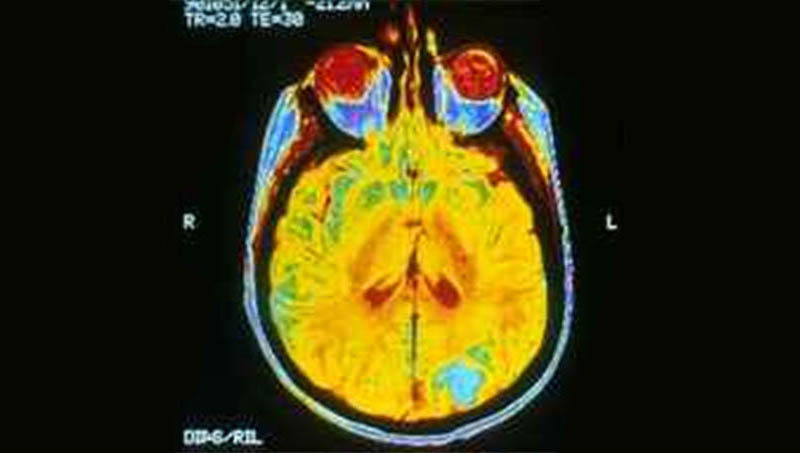

Képünk illusztráció